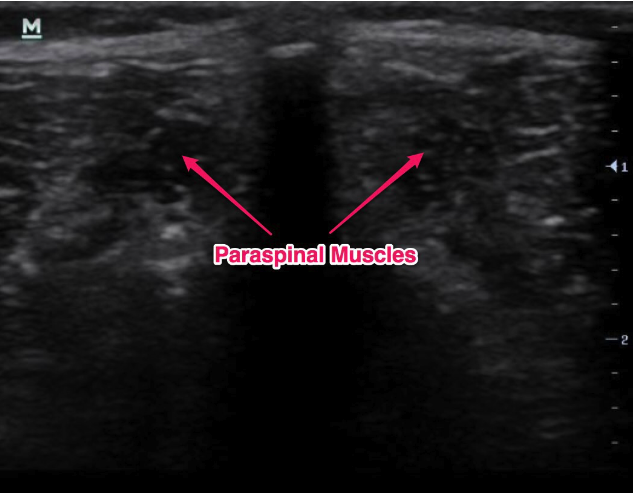

Estudo imagiológico: ecografia abdominal, TC ou RM